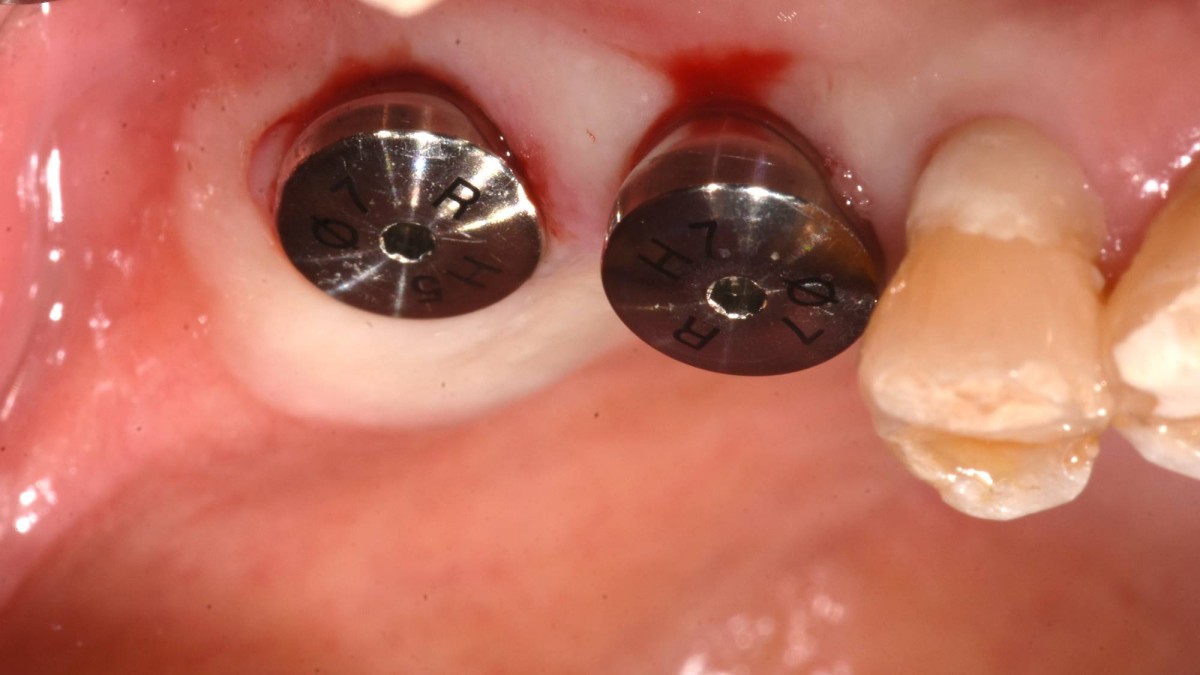

Socket Lift and Implant Placement in the right maxilla.